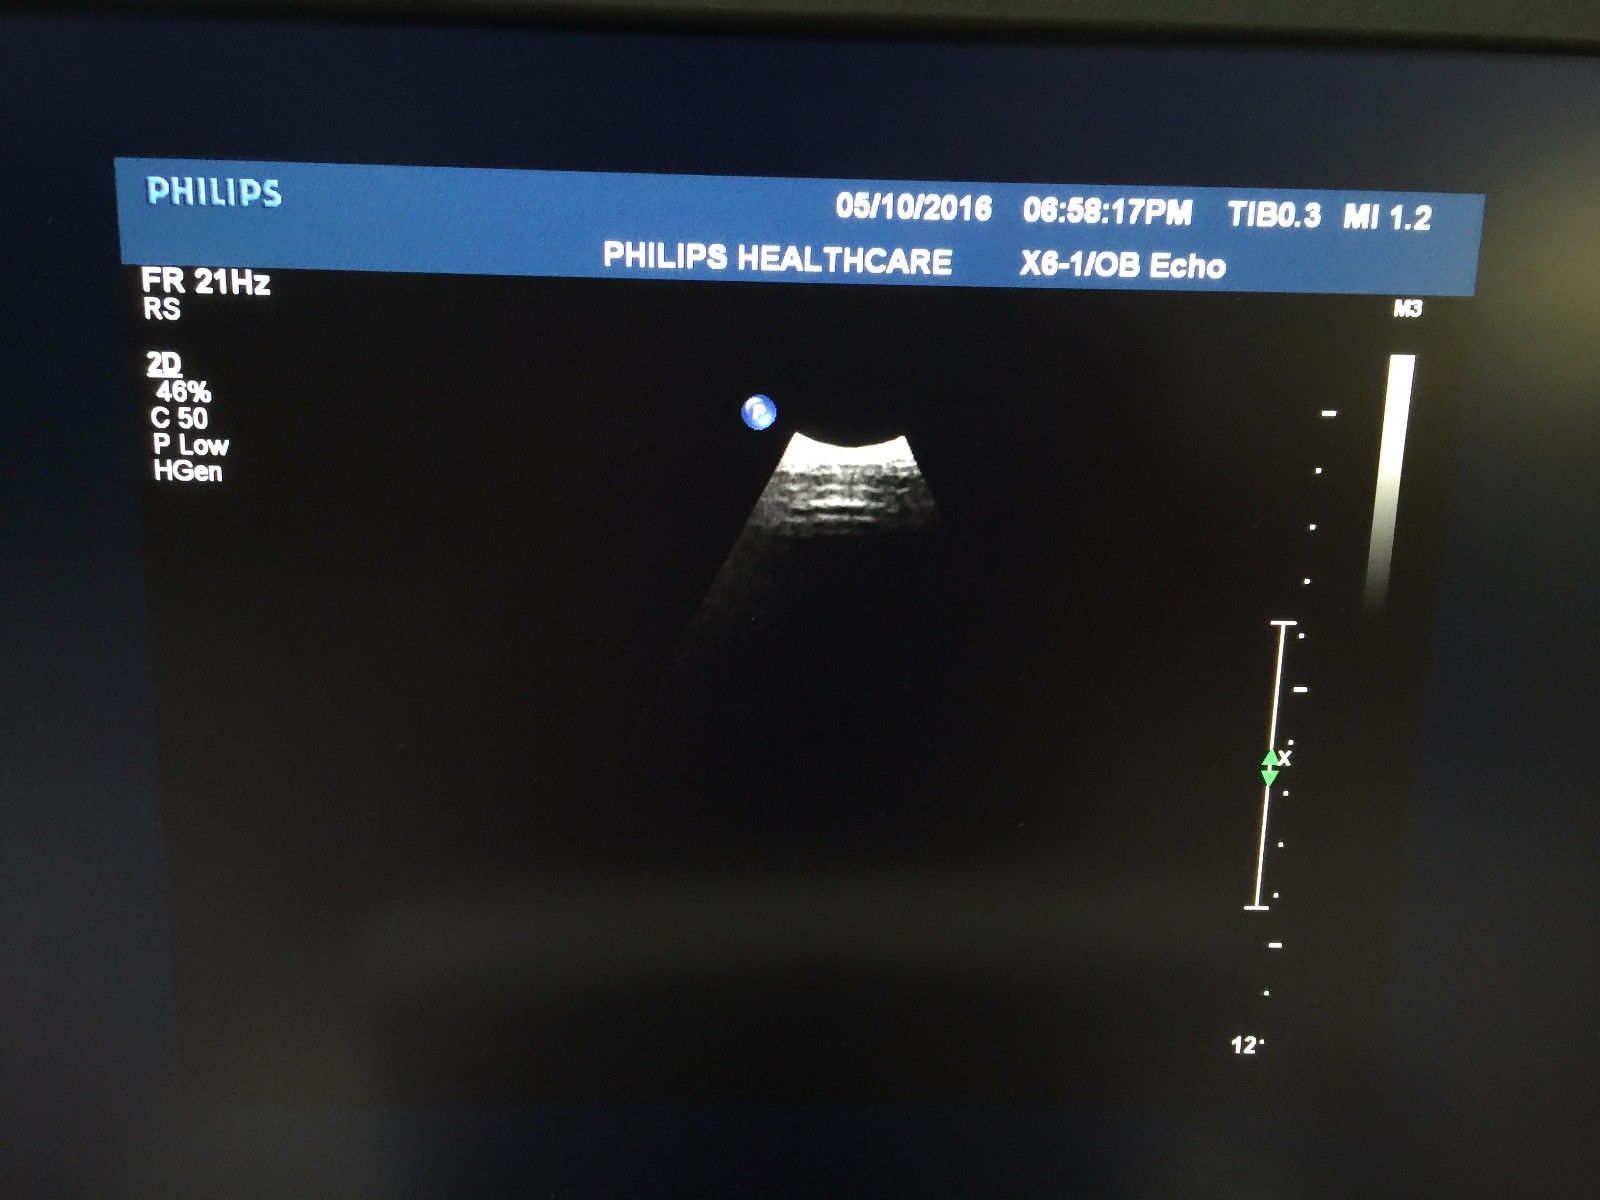

Philips X5-1 Explora Ultrasound Transducer

Sale price$ 45,572.30